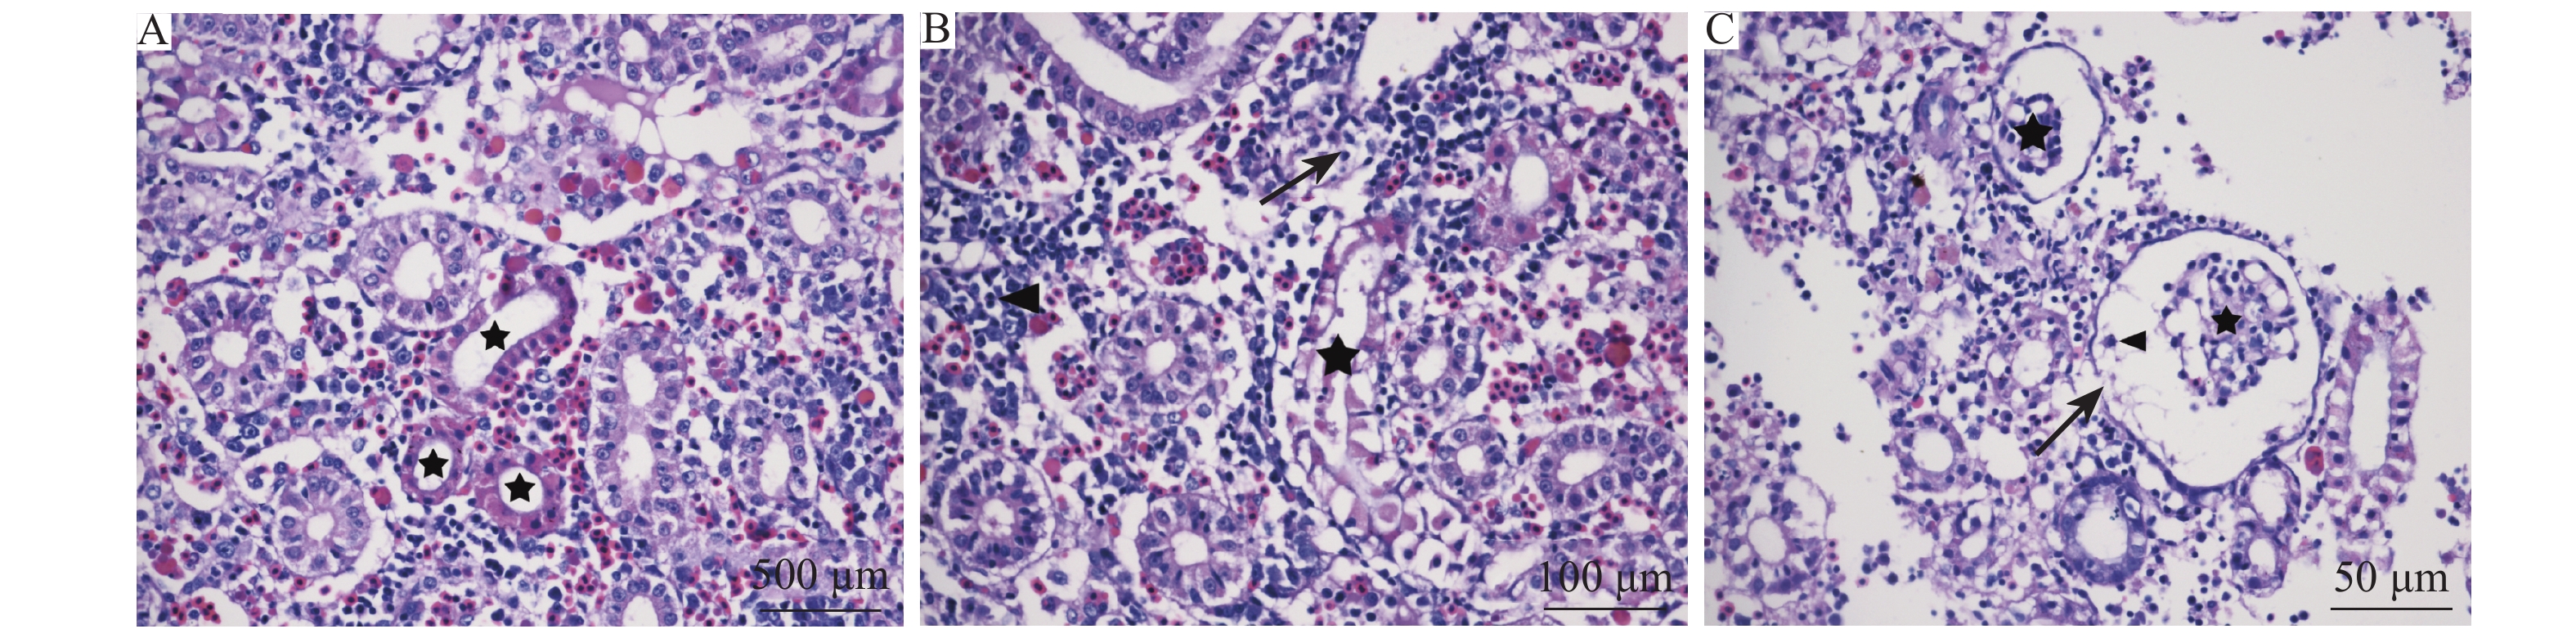

结果  该出血溃疡症的靶器官主要为脾脏、肾脏、肝胰脏、肠道以及皮肤肌肉。主要表现为严重的血管反应,实质细胞可见肿胀、变性、坏死;而胃、脑和心脏病变较轻,仅有轻微的炎症;鳃丝、眼球和鳔等未见明显病变。所有的患病个体均出现中度至重度出血性坏死性脾炎、中度肾炎、轻度至中度坏死性肝胰腺炎和肠炎。患病斑点叉尾鮰体内未检测到寄生虫、细菌以及CCV。

Result  The spleen, kidney, hepatopancreas, intestine, skin and muscle were the main target organs of hemorrhagic ulcer. The main syndrome was severe vascular response with degeneration and necrosis of the parenchymal cells. Stomach, brain and heart had minor damages with slight inflammation, and gill filaments, eyeballs and swim bladder did not have obvious pathological changes. The diseased individuals displayed moderate to severe hemorrhagic necrotic spleen inflammation, moderate nephritis, and mild to moderate necrotic hepatopancreatitis and necrotic enteritis. No parasite, bacteria, or CCV was detected in diseased catfish.